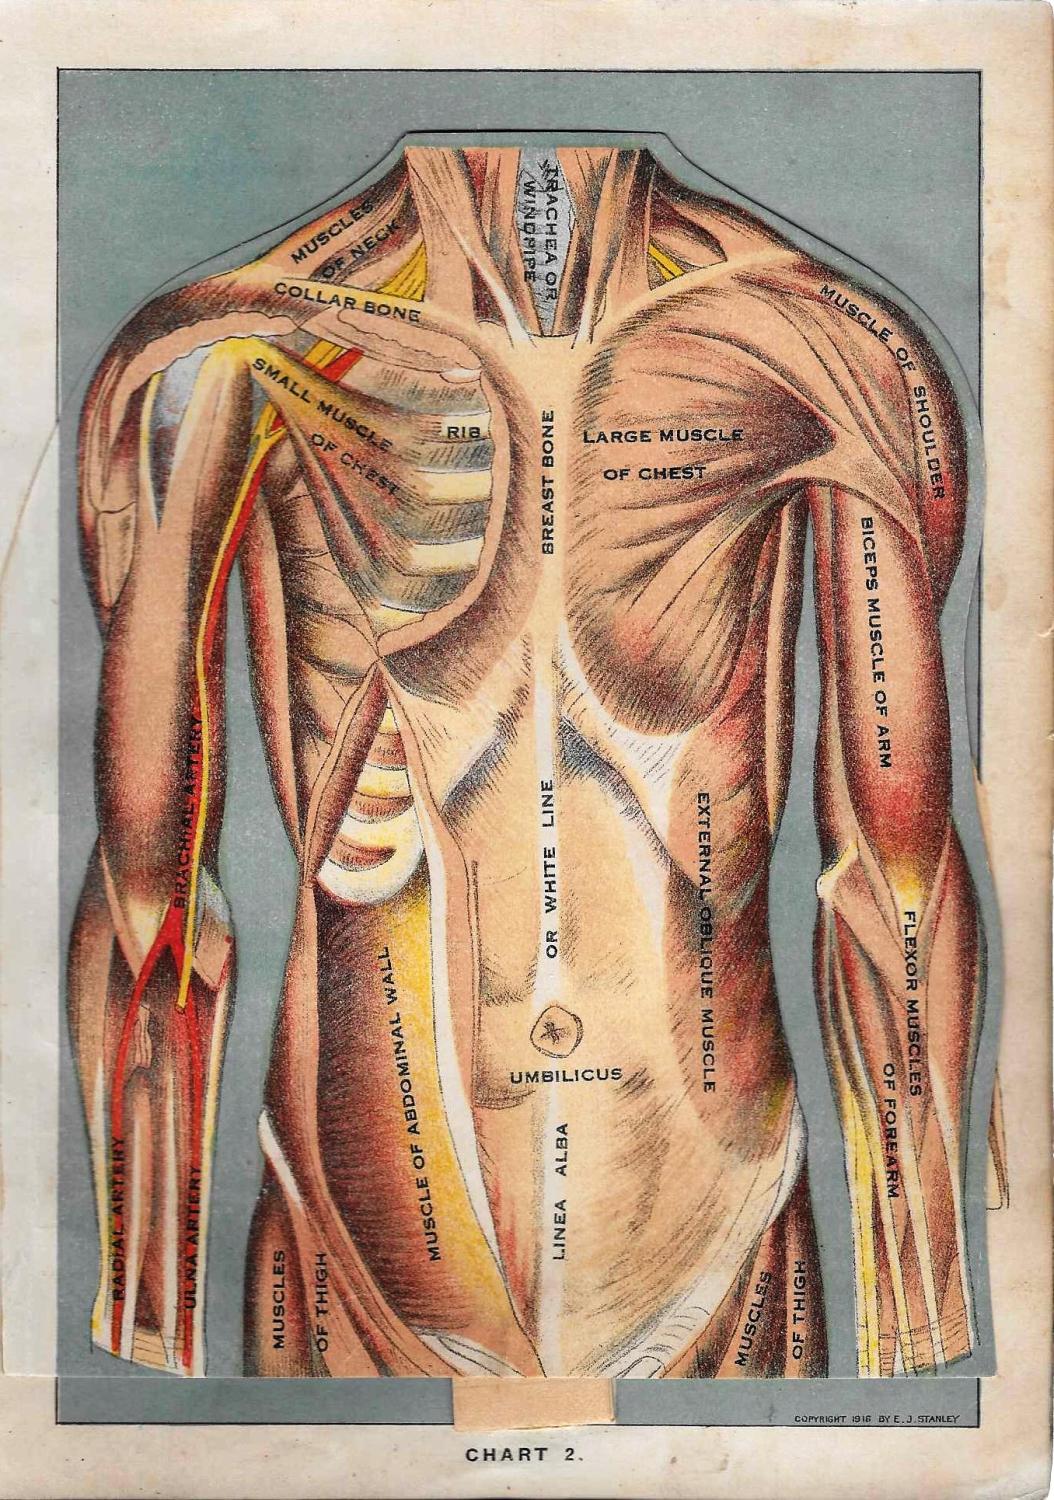

Female Upper Torso Anatomy - anatomy rigged torso ma : The pectoral muscles are divided into  29 best images about Muscle System on Pinterest | Crests, Human anatomy and Arches

Human Female Torso Anatomy 3D Model MAX OBJ 3DS FBX C4D LWO LW LWS - CGTrader.com  Antique Human Anatomy Print of Human Female Torso by Stanley, E. J: StrPublishing Company

Antique Human Anatomy Print of Human Female Torso by Stanley, E. J: StrPublishing Company  How to Draw the Female Torso, an in-Depth Guide â GVAAT'S WORKSHOP

Torso Anatomy Chart / Torso Anatomy Chart : Anatomy Chart Trigger Point Charts - Paka Lapan  Pin by sindo vazquez on Anatomia dibujo | Anatomy sketches, Anatomy drawing, Human anatomy art

Torso Anatomy Plate French Vintage Original Print 1920's - Etsy  FIGURE PROCESS AND TORSO REF by HumanNature84 on DeviantArt | Figure sketching, Anatomy tutorial